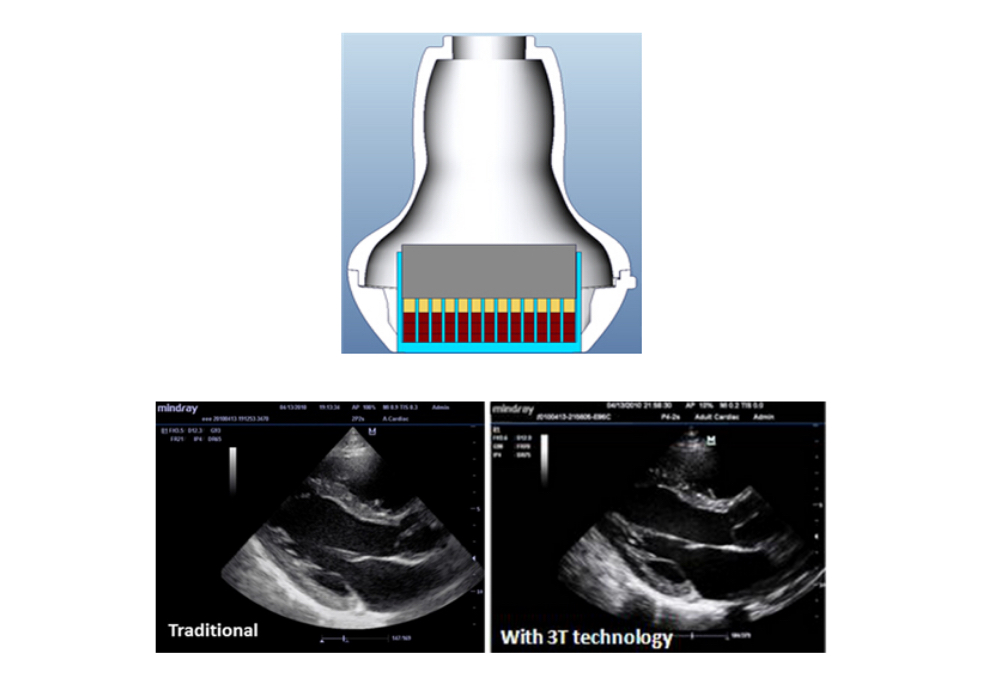

3T Transducer Technology?

MindrayŌĆÖs patent transducer technology to increase image bandwidth and transmission efficiency.

┬Ę Triple-matching layer design for higher sensitivity, wider bandwidth, and improved S/N

┬Ę Total-cut design for lower cross-talk noise, better directivity, and improved lateral resolution

┬Ę Thermal-control design for better acoustic transmission